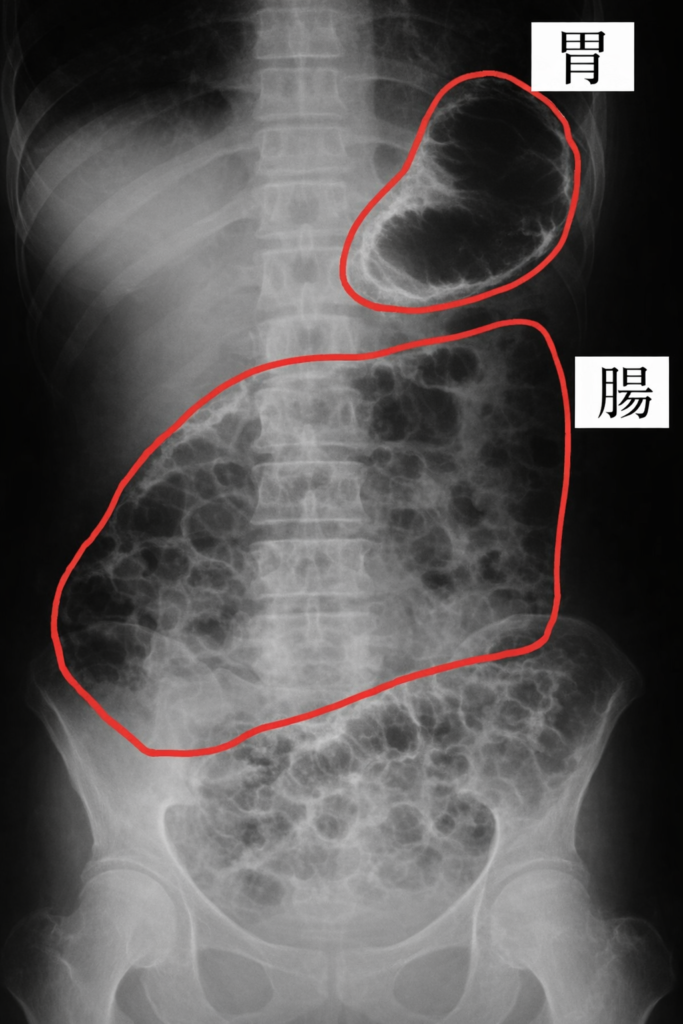

ガスが溜まってお腹が痛くなるような場合は、病院で医師の判断により、必要に応じて腹部レントゲン検査が行われることもあります。

*画像はイメージです(AIで作成)